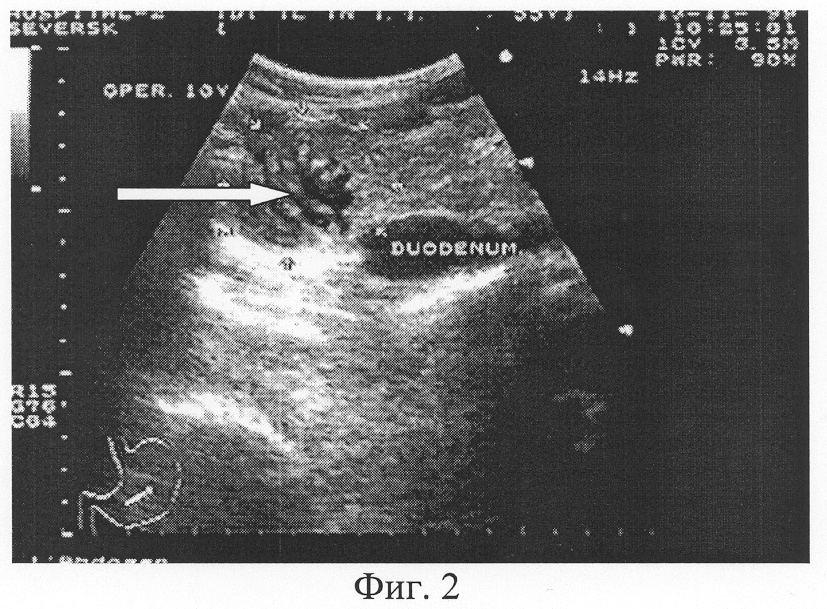

Нисходящая часть двенадцатиперстной кишки заканчивается нижним изгибом, от которого начинается нижняя горизонтальная часть, расположенная ниже поджелудочной железы и брыжейки поперечной ободочной кишки и имеющая косовосходящее направление. Длина нижней горизонтальной части довольно вариабельна – от 1 до 9 см. Визуализация нерасширенной нижней горизонтальной части в процессе ультразвукового исследования может вызывать трудности, причем на эхограмме идентификация этого отдела кишки еще более сложна. Просвет заполненной двенадцатиперстной кишки на всем ее протяжении (при прохождении порции жидкости или пищи) составляет в норме не более 2,0-2,5 см, толщина стенки – 2-4 мм. При использовании высокоразрешающего ультразвукового аппарата и перпендикулярной по отношению к стенке кишки плоскости сканирования удается визуализировать пятислойную структуру стенки двенадцатиперстной кишки, аналогичную морфологической структуре стенки органа. Обычно после заполнения кишки жидкостью удается визуализировать циркулярные складки слизистой кишки [1] (Фиг.2). Прохождение порции жидкости, попавшей в двенадцатиперстную кишку, осуществляется у здоровых обследуемых быстро – за 10-15 с, иногда с непродолжительными остановками и маятникообразными движениями [2].

Фиг.2. Трансабдоминальное ультразвуковое исследование двенадцатиперстной кишки. Четко визуализируются циркулярные складки слизистой ДПК на фоне жидкости в просвете (стрелка).